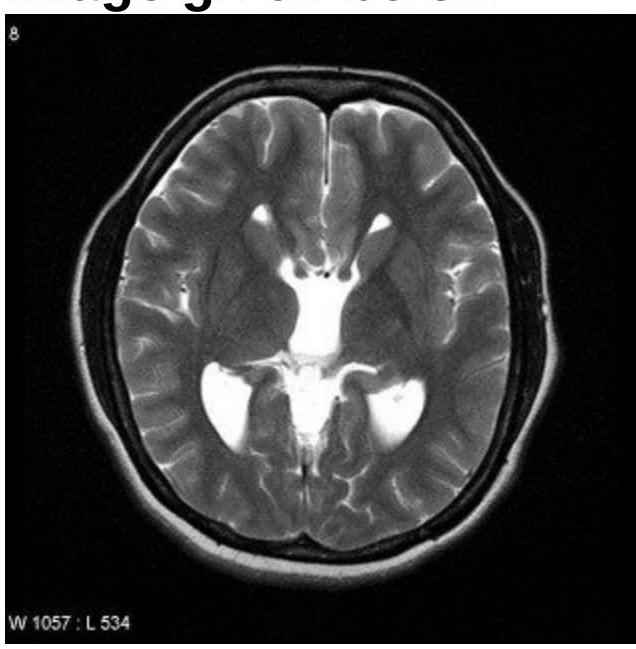

Identify the condition based on the provided image.

Explanation: ***Callosal dysgenesis*** - The image shows **colpocephaly**, characterized by **dilatation of the posterior horns** of the lateral ventricles and narrowing of the anterior horns. This is a classic MRI finding in callosal dysgenesis. - The absence or partial formation of the **corpus callosum** leads to a high-riding third ventricle and parallel lateral ventricles, which are often visualized alongside colpocephaly. *Dandy-Walker syndrome* - Characterized by a **cystic dilatation of the fourth ventricle** that fills the posterior fossa, leading to an upward displacement of the tentorium. - This condition involves agenesis or hypoplasia of the **cerebellar vermis**, which is not depicted in this image. *Aicardi syndrome* - Aicardi syndrome is characterized by the triad of **agenesis of the corpus callosum**, **chorioretinal lacunae**, and **infantile spasms**. - While it includes agenesis of the corpus callosum, the image alone does not provide evidence of the ocular or seizure components of Aicardi syndrome. *Septo-optic dysplasia* - This condition is defined by the **triad of optic nerve hypoplasia**, **pituitary hormone abnormalities**, and **midline brain defects**, specifically hypoplasia or absence of the septum pellucidum. - The image does not show features specific to optic nerve hypoplasia or the typical midline cysts or absent septum pellucidum characteristic of septo-optic dysplasia.